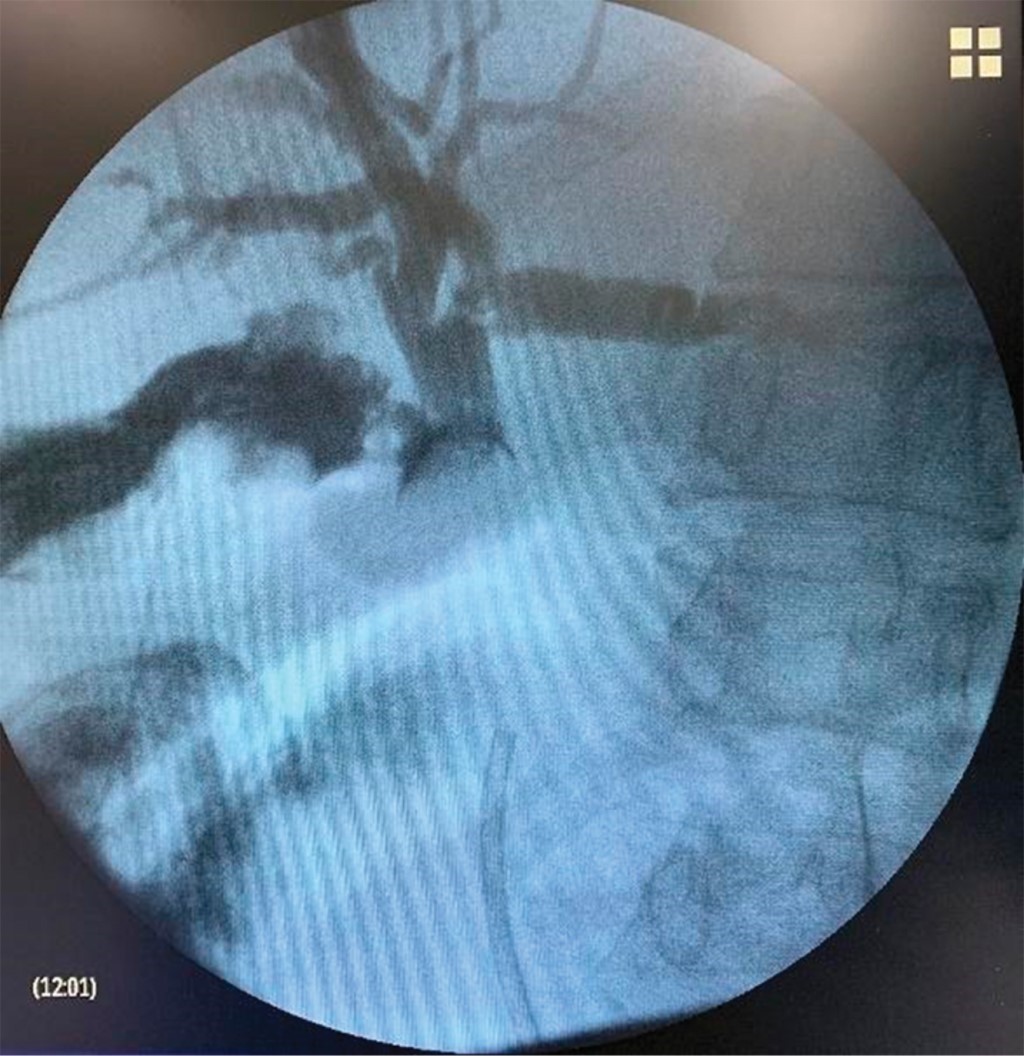

Colon por enema, cáncer colón, diverticulitis Enema opaco de doble